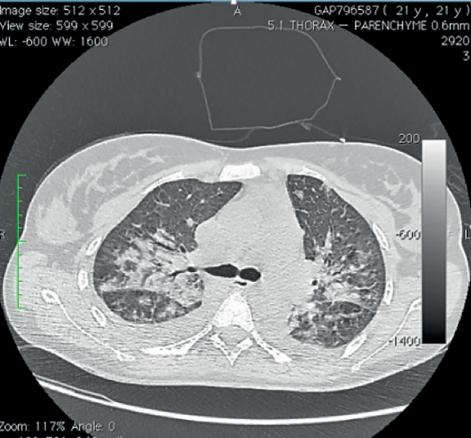

Le scanner cervico-thoracique (fig. 1 et 2 ) montre une thrombose de la veine jugulaire interne gauche ainsi qu’un épanchement pleural bilatéral et une pneumopathie des deux côtés sur emboles septiques, permettant de poser le diagnostic de syndrome de Lemierre.

L’aspect radiologique typique est celui de notre observation. Les abcès pulmonaires, multiples et disséminés par voie hématogène, sont évocateurs. Ils font rechercher une thrombose jugulaire ou de ses collatérales.